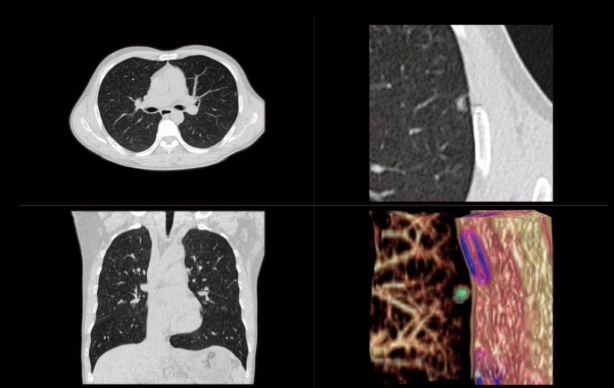

6、低剂量胸部CT检查:

剂量仅为常规CT的26%甚至更低,大大降低了对受检者的伤害;尤其适用于肺癌早期筛查、肺内结节的定期追踪,以及未成年人的疾病诊疗。